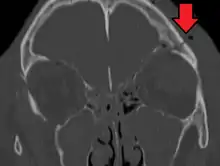

Basilar skull fracture

A basilar skull fracture is a break of a bone in the base of the skull.[1] Symptoms may include bruising behind the ears, bruising around the eyes, or blood behind the ear drum.[1] A cerebrospinal fluid (CSF) leak occurs in about 20% of cases and can result in fluid leaking from the nose or ear.[1] Meningitis is a complication in about 14% of cases.[2] Other complications include cranial nerve or blood vessel injury.[1]

They typically require a significant degree of trauma to occur.[1] The break is of at least one of the following bones: temporal bone, occipital bone, sphenoid bone, frontal bone, or ethmoid bone.[1] They are divided into anterior fossa, middle fossa, and posterior fossa fractures.[1] Facial fractures often also occur.[1] Diagnosis is typically by CT scan.[1]

Basilar skull fractures include breaks in the posterior skull base or anterior skull base. The former involve the occipital bone, temporal bone, and portions of the sphenoid bone; the latter, superior portions of the sphenoid and ethmoid bones. The temporal bone fracture is encountered in 75% of all basilar skull fractures and may be longitudinal, transverse or mixed, depending on the course of the fracture line in relation to the longitudinal axis of the pyramid.[5]